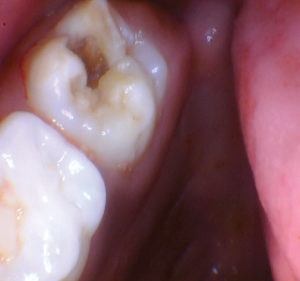

Caso 2

Un nuevo paciente de 7 años presentó una importante descomposición e hipocalcificación en el primer molar permanente superior derecho. Durante mucho tiempo se ha demostrado que los primeros molares permanentes cariados e hipocalcificados en pacientes pediátricos le dan al profesional un dilema restaurador difícil. ¿Deberíamos intentar prepararnos y restaurarlos conservadoramente? ¿Deberíamos ser más agresivos y restaurar con una cobertura completa como una corona de acero inoxidable bien adaptada? Activa proporciona una gran alternativa en estos casos, con liberación de calcio, fosfato y fluoruro junto con alta resistencia y resistencia a la fractura.

Figura 2. Una vez que se excavó la descomposición y se colocaron los márgenes en superficies sólidas, se colocó un bisel pesado en el esmalte para aumentar la resistencia de la unión y la integridad marginal. El área oscura central era sólida. El diente estaba revestido con una base / revestimiento Activa. |